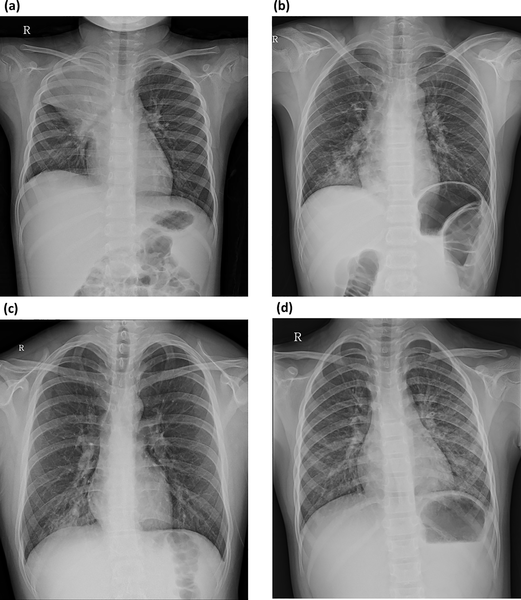

Mycoplasma

2.covid 19

ยังคงประมาทไม่ได้สำหรับ COVID-19 ซึ่งเป็นโรคระบาดที่เกิดจากไวรัสโคโรนาสายพันธุ์ใหม่ที่ชื่อ SARS-CoV-2 ซึ่งมีผลกระทบรุนแรงต่อมนุษย์ทั่วโลกตั้งแต่ปี 2019 จนถึงปัจจุบัน โรคนี้สามารถแพร่กระจายได้ผ่านการติดต่อกันระหว่างคนผ่านทางละอองที่แพร่กระจายจากการไอหรือจามของผู้ติดเชื้อ หรือผ่านการสัมผัสกับพื้นผิวที่มีเชื้อปนเปื้อน

อาการของโรค COVID-19 ส่วนใหญ่เริ่มต้นด้วยไข้ อาการไอ หายใจลำบาก คัดจมูก  ครั่นเนื้อครั่นใจ เบื่ออาหาร และมีความเสี่ยงที่จะเกิดภาวะแทรกซ้อนรุนแรงได้ เช่น ปอดบวม วิกฤตต่อเนื่องของระบบไต หรือภาวะติดเชื้อระบบประสาทส่วนกลางและอย่างอาการสำคัญของสายพันธุ์ XBB.1.16 (สายพันธุ์ที่ระบาดช่วงปลายปี 2022 ถึง ต้นปี 2023 ) อาการที่พบส่วนใหญ่ ได้จะแก่ มีไข้สูง หวัดคัดจมูก ไอ ผื่นคัน ปวดศีรษะ ปวดตามร่างกาย จมูกไม่ได้กลิ่น อาจมีอาการท้องเสียร่วมด้วย เยื่อบุตาอักเสบ คล้ายตาแดง คันตา ขี้ตาเหนียว ลืมเปลือกตาไม่ขึ้น

สำหรับการป้องกันและควบคุมโรค COVID-19 รวมถึงการเฝ้าระวังการแพร่กระจายของไวรัส มีการแนะนำให้ล้างมือบ่อยๆ ใช้แอลกอฮอล์เจลทำความสะอาดมือ สวมหน้ากากอนามัย  เว้นระยะห่างกันอย่างน้อย 1 เมตร และหลีกเลี่ยงการไปที่พื้นที่คับคั่งหรือมีคนมาก เช่น สถานที่ที่ไม่จำเป็น หรือสถานที่ที่มีการรวมกลุ่มคนมาก